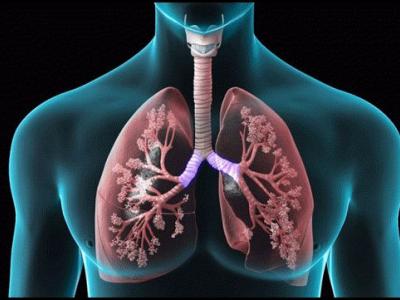

Coronavirus medicine: कोरोना फेफड़ों पर अटैक करता है और यह दवा फेफड़ों से फैट हटाकर उन्हें स्वस्थ करती है

फेफड़ों के फैट को खत्म करती है दवा

फेफड़ों पर अटैक करता है कोरोना

दोनों शोधकर्ताओं ने देखा कि सार्स-सीओवी-2 स्वयं को बढ़ाने के लिए मरीजों के फेफड़ों में किस तरह से बदलाव करता है। उन्होंने पाया कि वायरस कार्बोहाइड्रेट को जलने से रोकता है जिसके परिणामस्वरूप फेफड़ों की कोशिकाओं में वसा का जमाव हो जाता है और यही परिस्थिति वायरस के बढ़ने के लिए अनुकूल होती है।

उन्होंने कहा, 'इसीलिए डायबिटीज और हाई कोलेस्ट्रॉल से पीड़ित लोगों के कोविड-19 की चपेट में आने की आशंका अधिक होती है।' फेनोफाइब्रेट फेफड़ों की कोशिकाओं को फैट जलाने में मदद करती है और इस तरह इन कोशिकाओं पर वायरस की पकड़ कमजोर हो जाती है।